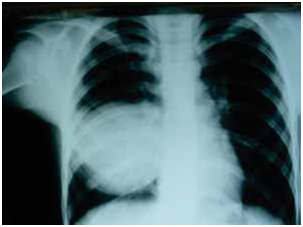

After discharge, all patients were treated with X-ray after 6 months of primary therapy. The criteria for radiological improvement were the loss of shaded cysts, and the resorption of postoperative pericystic inflammation and pleural reaction (Figure 12­–15).

Figure 13 Postoperative x-ray, pericystic cavity non-capitonnage method.

Figure 14 Postoperative x-ray cavity capitonnage method.

Of the 80 patients treated in this study, we did not have a single case of relapse. Considering the large number of complicated, gigantic and multiple cleaners in both groups, we consider this result satisfactory. The literature published a recurrence rate of 2-12% while Sayir and associates had a recurrence rate of 1.4%.36 We further analyzed the finding of a control chest X-ray of the lung image 6 months after surgery. The success of the procedure was characterized by radiological improvement after 6 months. Radiological improvement was characterized by absence of atelectasis, loss of shadow operated cysts and resorption of postoperative cystic inflammation.

Based on the analyzed data of radiological recording in the investigated group, no subjects with lung atelectasis were recorded after surgery, while in the control group this complication occurred in 7 subjects. In the examined group, there was a disappearance of shadow of operable cyst in 31 subjects, while in the control group there were 20 respondents with shadow disappearing after 6 months. In the investigated group, there was a resorption of postoperative inflammation in 37 subjects, while in the control group there were 27 subjects who recorded resorption of postoperative pericystic inflammation. Following three radiological parameters, 6 months after surgery: the presence of atelectasis, the disappearance of shadow-operated cysts, and the resorption of postoperative periclinic inflammation, we concluded that the regression of radiological changes was significantly more pronounced in the test (capitonnage) compared to the control group (non-capitonnage).